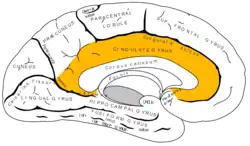

Giro cingulado

Hemisferio cerebral izquierdo: localización del giro cingular. | ||

El giro cingulado, también conocido en neuroanatomía como giro del cíngulo, circunvolución del cíngulo, giro cingular, gyrus cinguli[1] o —abreviadamente— cingulum, es una circunvolución o gyrus en el área media del cerebro que cumple funciones determinantes en la actividad cerebral del sistema límbico; se encuentra hacia el borde o limbo de la corteza cerebral.

Disposición anatómica

Envuelve parcialmente al cuerpo calloso (corpus callosum) que es por su parte el nexo entre los dos hemisferios cerebrales; concretamente el giro cingulado está delimitado por un área llamada cisura callosa marginal o surco cingulado. La parte inferior del giro cingulado se enrolla sobre sí misma (con forma de espiral logarítmica) y resulta ser la quinta circunvolución del área temporal del cerebro, El uncus (palabra que en latín significa gancho debido a su forma), la parte del giro cingulado relacionada con la corteza cerebral es denominada corteza cingulada o córtex cingulado.

Se encuentra en la porción marginal de la corteza cerebral, en la superficie interna del hemisferio cerebral, y nace a nivel del cíngulo del cuerpo calloso, donde se une con el extremo anterior de la circunvolución perpendicular interna y forma un lobulillo diminuto denominado encrucijada olfatoria o centro de Broca. Desde el pico, se dirige primero de atrás hacia adelante, luego rodea la rodilla del cuerpo calloso y se prolonga hasta el rodete. En este punto se continúa con el giro parahipocampal. Forma una parte importante del sistema límbico.[2]

Se halla limitado por el "surco calloso marginal" hacia arriba y por el "surco del cuerpo calloso" por abajo. En su parte posterior está separada del lóbulo cuadrado por un pequeño surco anteroposteior de segundo orden que es el llamado "surco subparietal", prolongación hacia atrás de la "cisura callosomarginal".

La circunvolución del cuerpo calloso se origina al nivel del pico del cuerpo calloso y se dirige hacia adelante; rodea luego de abajo arriba la rodilla de dicho cuerpo y se vuelve hacia atrás, siguiendo la cara superior del cuerpo calloso hasta alcanzar el rodete de este. Aquí termina al continuarse con la circunvolución del hipocampo por una porción estrecha que forma el pliegue de paso entre el lóbulo temporal y la circunvolución del cuerpo calloso, y que recibe el nombre de "pliegue temporolímbico".